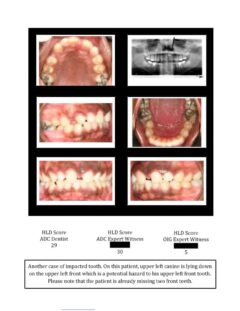

So here again are photos of children’s teeth that were pre-approved for treatment by the state’s Medicaid claims administrator TMHP/ACS, that HHSC-OIG now claims were fraudulently scored by Medicaid dental providers. These cases are from the SOAH hearings that have been completed for Harlingen Family Dentistry and Antoine Dental Center. The SOAH courts found both practices innocent of any allegation of Medicaid fraud or misrepresentation. The photo pages show the attending dentist’s HLD score, the dentist’s expert witness score and the OIG expert’s score.

Harlingen Family Dentistry